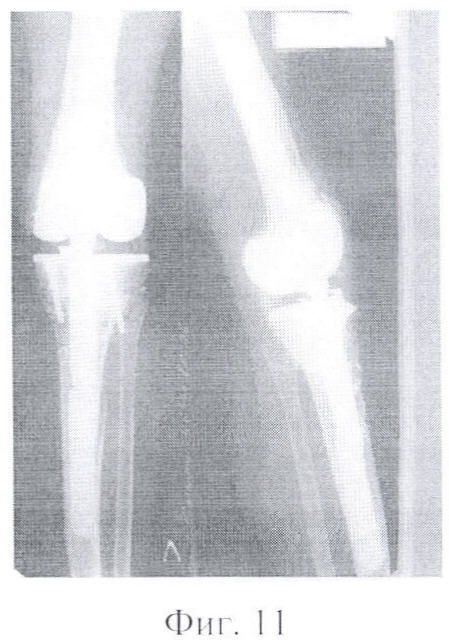

Фигура 11 – контрольная рентгенограмма реэндопротезированного левого коленного сустава через 12 месяцев, сращение структурных губчато-кортикальных аллотрансплантатов бедренной и большеберцовой костей с материнским ложем. Вид спереди, вид сбоку.

Через 12 месяцев на контрольной рентгенографии отмечается сращение структурных аллотрансплантатов с материнским ложем (фиг.11).